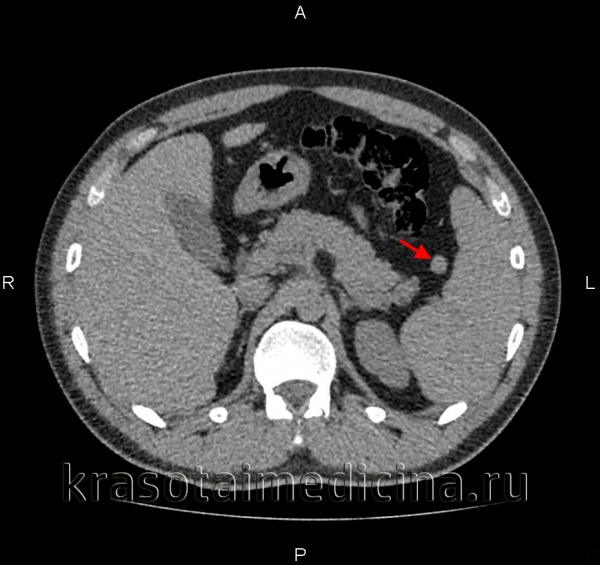

о Единичная однокамерная киста с плотностью, близкой к плотности воды, и четкими контурами:

- Имеет тонкую стенку, четко отграничена от неизмененной ткани селезенки

- В кисте отсутствует солидный компонент (узлы), участки накопления контраста внутри или на периферии кисты

о Некоторые кисты могут иметь перегородки, трабекулы, внутренние включения некротического дебриса, толстую стенку:

- Плотность кист при наличии геморрагического содержимого или белка может быть ↑ плотности простой жидкости

о В кистах могут обнаруживаться обызвествления в виде «яичной скорлупы» либо широкие кальцинаты по периферии